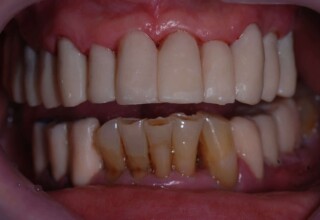

Ολική Στοματική Αποκατάσταση σε Εμφυτεύματα με διαφορετική προσέγγιση στην Άνω και Κάτω Γνάθο

Κάτω γνάθος: εξαγωγές, άμεση τοποθέτηση εμφυτευμάτων και άμεση φόρτιση(την ίδια ημέρα) με προσωρινή γέφυρα

Άνω γνάθος: σταδιακές εξαγωγές, σταδιακή τοποθέτηση εμφυτευμάτων και σταδιακή ενσωμάτωση τους στην προσωρινή γέφυρα ώστε η ασθενής να μην μείνει ούτε μια ημέρα χωρίς αποκατάσταση. Στόχος η συνεχής λειτουργική και αισθητική αποκατάσταση της ασθενούς χωρίς άμεση φόρτιση των εμφυτευμάτων λόγω ανατομικών ιδιαιτεροτήτων.

Χρησιμοποιήθηκαν παλαιές χαμογελαστές φωτογραφίες της ασθενούς γιατί είχε χαθεί τελείως το φυσικό σχήμα των δοντιών εξαιτίας των πολλαπλών προσθετικών προσπαθειών που είχαν γίνει στο παρελθόν. Μεταφέρθηκε στην προσωρινή γέφυρα η σχέση των φυσικών δοντιών μεταξύ τους άλλα και με τα χείλη. Δοκιμάστηκε η φώνηση και η μάσηση με δυο διαφορετικές προσωρινές άνω γέφυρες και εκτιμήθηκε η αισθητική απόδοση τους. Αφού επιτεύχθηκαν σε βαθμό ικανοποιητικό η φώνηση και η αισθητική εμφάνιση της οδοντοφυΐας, η προσωρινή αποκατάσταση χρησιμοποιήθηκε ως οδηγός για την τελική.

Αρχικό